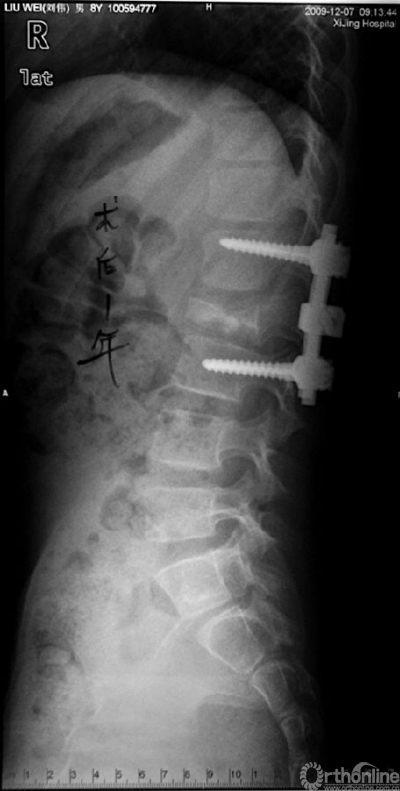

图3 术后1年腰椎侧位片,L2椎体高度部分恢复。